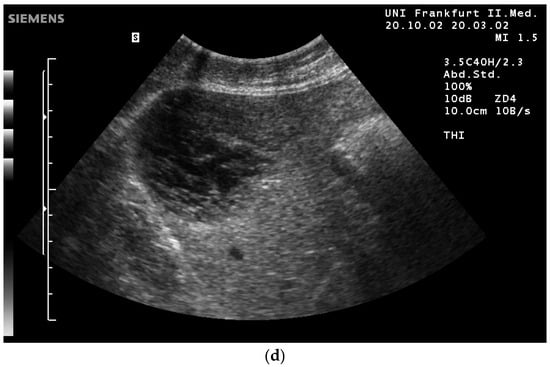

- The combination with speckle filters available in all high-end devices, similar to the low-pass filters used by Bleck et al. (1994) for tissue visualization [5], also yields significantly improved visualization results (Figure 5, Figure 6 and Figure 7). In principle, applications with new visualized texture analyses, such as random field models, are also conceivable [76,77].

- Can be used together with THI

- Fischer, T.; Filimonow, S.; Taupitz, M.; Petersein, J.; Beyersdorff, D.; Bollow, M.; Hamm, B. [Image quality and detection of pathology by ultrasound: Comparison of B-mode ultrasound with photopic imaging and tissue harmonic imaging alone and in combination]. Rofo 2002, 174, 1313–1317. [Google Scholar] [CrossRef] [PubMed]